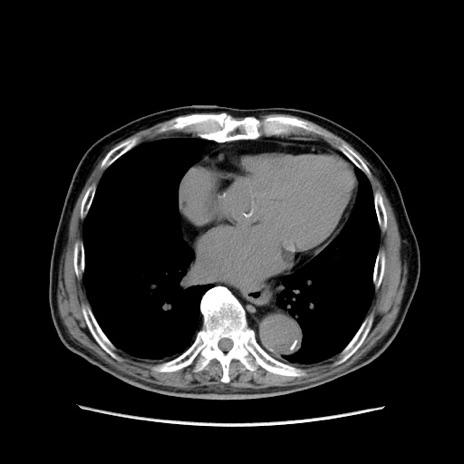

症例24(横断像)

【症例】80歳代男性

【主訴】左側腹部痛、嘔吐

【現病歴】本日早朝より左腹部に痛みあり。昼頃嘔吐認めたため、救急要請。

【既往歴】直腸癌(Mile手術)、胆摘

【身体所見】意識清明、BT 35.9℃、BP 221/93mmHg、SpO2 97%(RA) 、腹部:左ストーマ周囲に限局性の腹部膨隆あり。 膨隆部自発痛・圧痛あり・軟。

【データ】WBC 7700、CRP 0.09